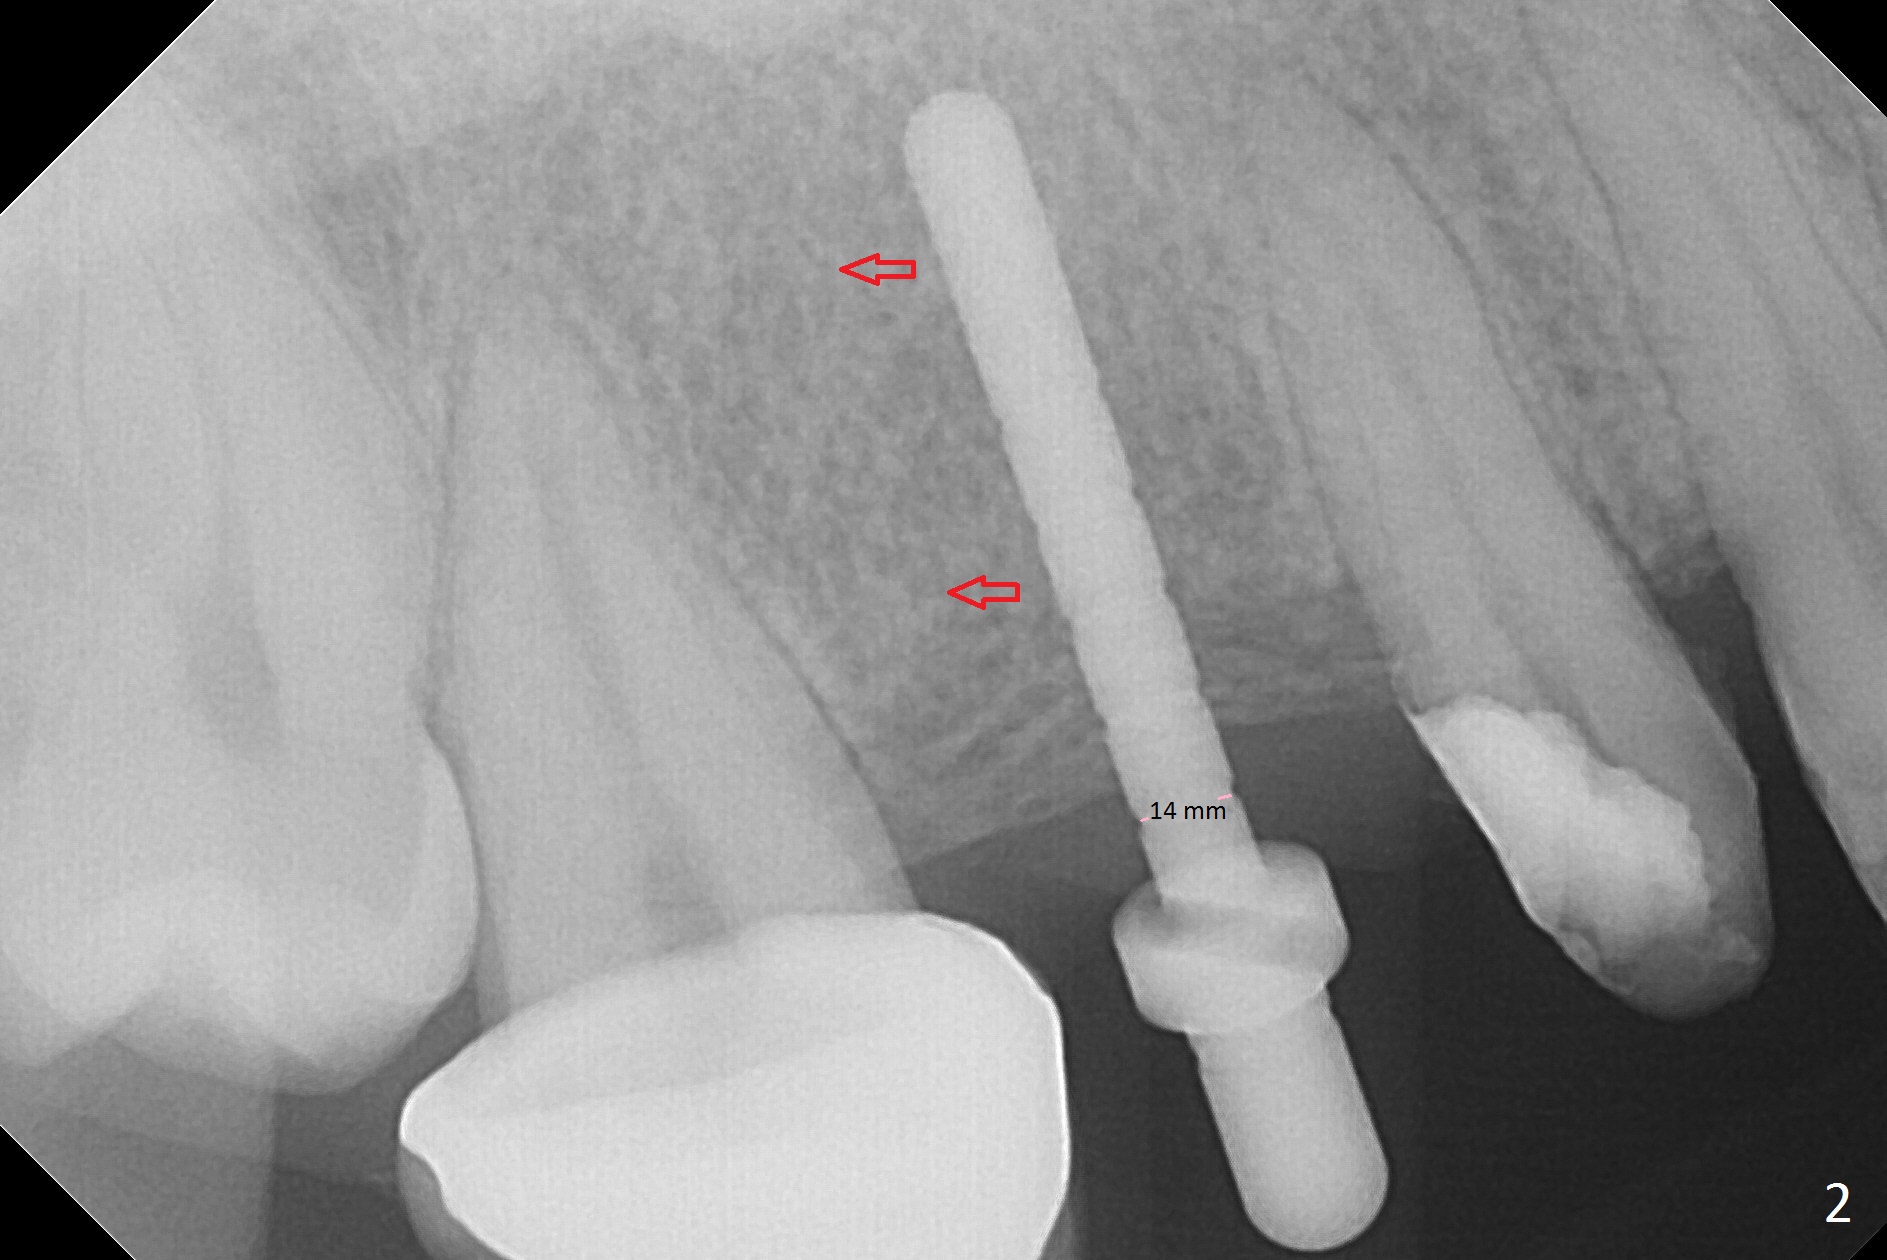

When the bridge is partially removed, the tooth #4 is found to have extensive caries. IRM is placed following carious removal (Fig.1). Magic Split testing shows that the bone density is high (flapless). Osteotomy is initiated by 1.6 mm drill, but the handle of the drill needs to shift mesial (Fig.1 red arrow). When the latter is done, the whole drill (2 mm) needs to move distal (Fig.2 double red arrows). When a 4.5x14 mm drill finishes the osteotomy, it is in the middle of the edentulous space (Fig.3). After use of 5 mm tap, a 5.3x14 mm implant cannot reach the depth (Fig.4,5). Following increase in osteotomy depth from 16 to 18 mm (gingival margin) until 5 mm drill in diameter, the implant placement level is more ideal (Fig.6,7, slightly subcrestal) with insertion torque maintaining at >55 Ncm. The sinus floor (Fig.4 arrowheads) may be penetrated when the osteotomy depth increases (Fig.7 *), but the sinus membrane remains intact.